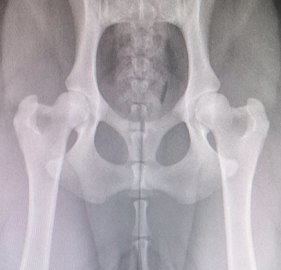

HD : A/A

AD : 0/0